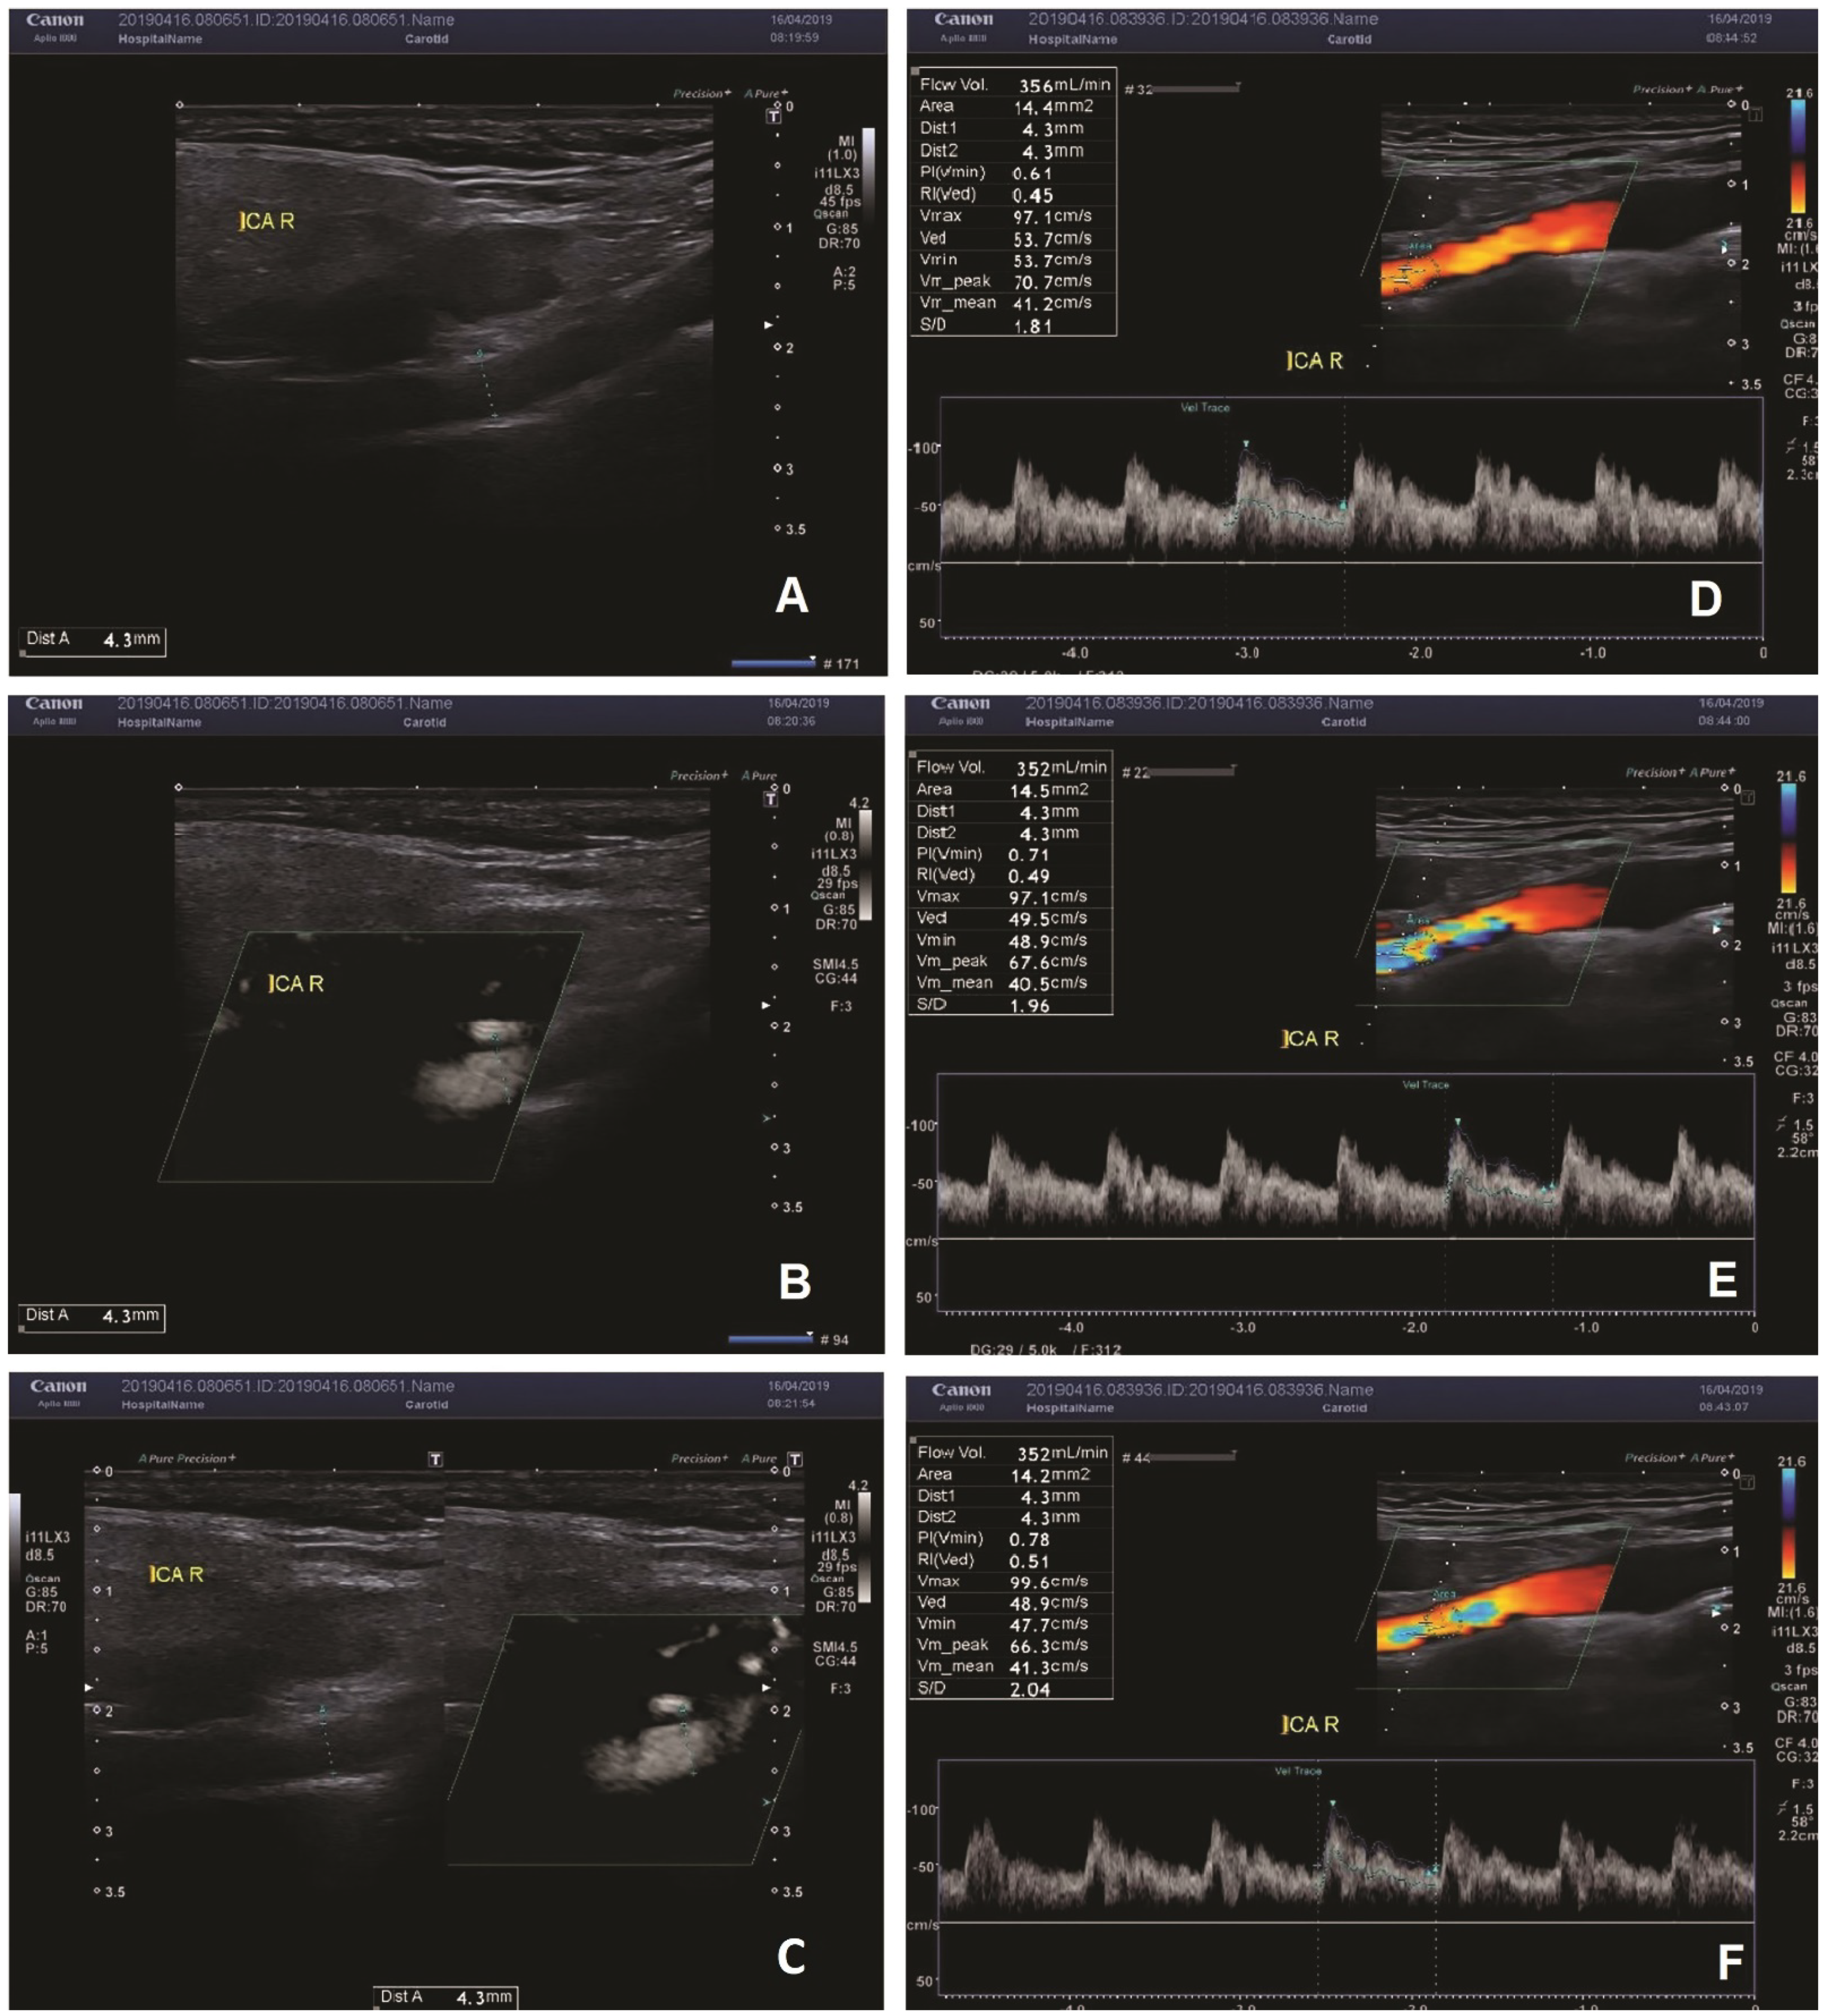

Figure 1.

(A–C)—the measurement of the diameter of the vessel with B-mode (A), SMI (B), combined B-mode/SMI (C). In all three measurements, the diameter of the vessel was 4.3 mm. (D–F)—measurement of the flow volume in the right ICA. The flow volume was 356 mL/min in one measurement (A), and 352 mL/min in two measurements (E,F).